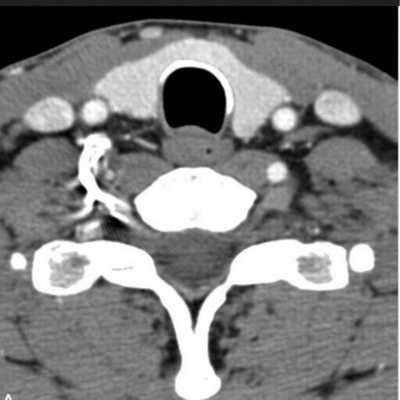

Компьютерная томограмма щитовидной железы

По компьютерным сканограммам специалист может судить о форме, размерах, строении и положении органа, состоянии лимфоузлов, паращитовидных желез, трахеи, пищевода, наличии или отсутствии патологических изменений.

Опухоль щитовидной железы на компьютерной томографии

В норме поперечные томограммы щитовидной железы показывают две однородные по структуре доли, прилегающие к трахее. Между ними узкий перешеек, рядом визуализируются мышцы, нервные и сосудистые пучки. Когда присутствуют опухоли, кисты, узловые образования, симметричность долей нарушается, строение органа становится гетерогенным (неоднородным).